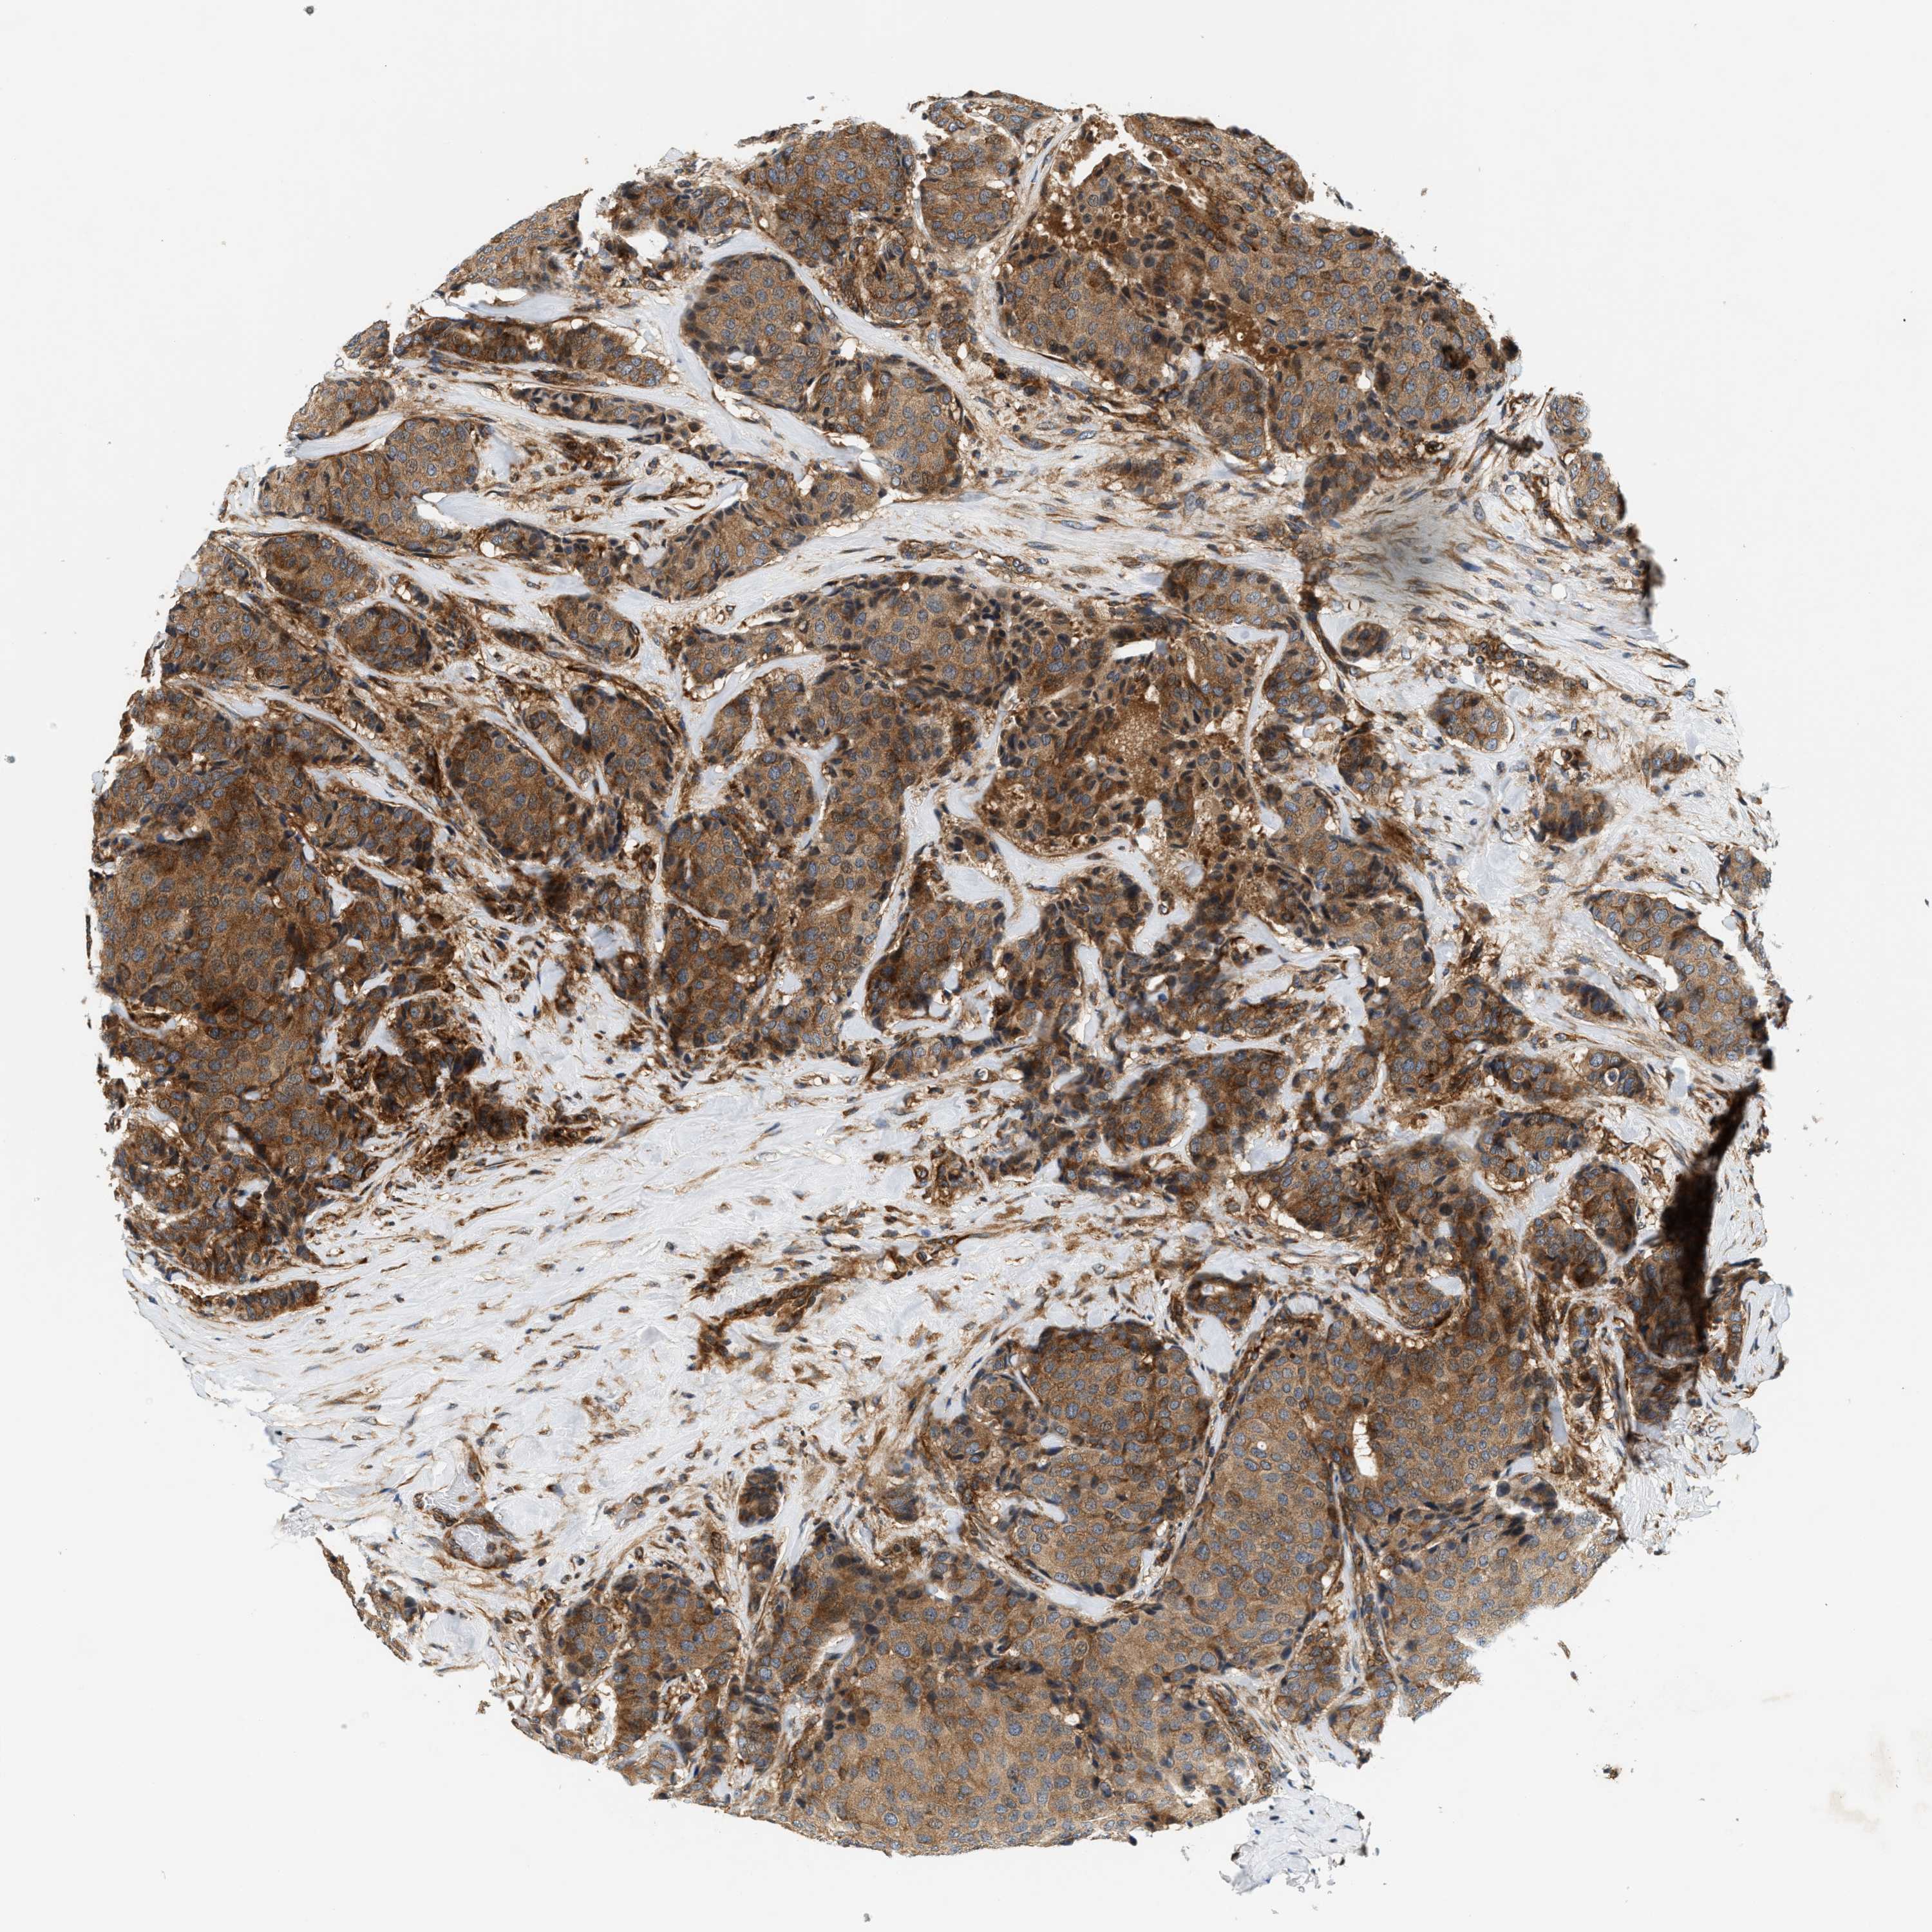

CANCER BREAST CANCER Show tissue menu

BRCA TCGA BRCA VALIDATION PROTEIN EXPRESSION

ANTIBODIES

AND

VALIDATION